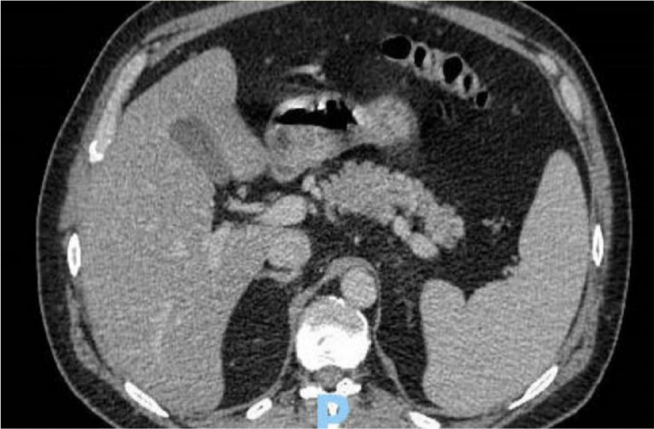

Pancreatic signet ring cell carcinoma (PSRCC) is a rare and aggressive subtype of pancreatic cancer with a dismal prognosis. We present the case of a 50-year-old male who, within six weeks, developed a pancreatic mass with liver metastases. Endoscopic ultrasound-guided biopsy confirmed PSRCC. The presentation of this tumour with distant metastasis after a negative computed tomography (CT) of the abdomen and pelvis six weeks prior underscores the highly aggressive nature of PSRCC and the crucial need for heightened clinical suspicion, especially in cases with persistent or atypical abdominal pain. This case highlights the limitations of current diagnostic modalities and emphasises the urgent need for further research into improved early detection methods, molecular characterisation and effective treatment strategies for this rare and lethal subtype of pancreatic cancer.

Learning points: Aggressive malignancy can become metastatic within six weeks of a negative CT scan.A CT scan may not detect a small pancreatic lesion <2 cm.